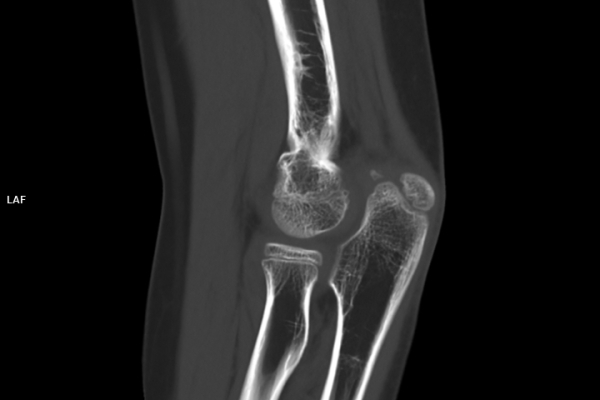

CT Untersuchung Bild

Die MRT (Magnetresonanztomographie) arbeitet mit Magnetfeldern und Radiowellen und eignet sich besonders für Untersuchungen der Weichteile wie Gehirn, Muskeln oder Gelenke. Die CT (Computertomographie) nutzt Röntgenstrahlen und liefert schnelle, hochauflösende Bilder, insbesondere für Knochen, Lunge oder innere Organe. Die Wahl der jeweiligen Untersuchung richtet sich an das individuelle Krankheitsbild und wird bei der Überweisung festgelegt.